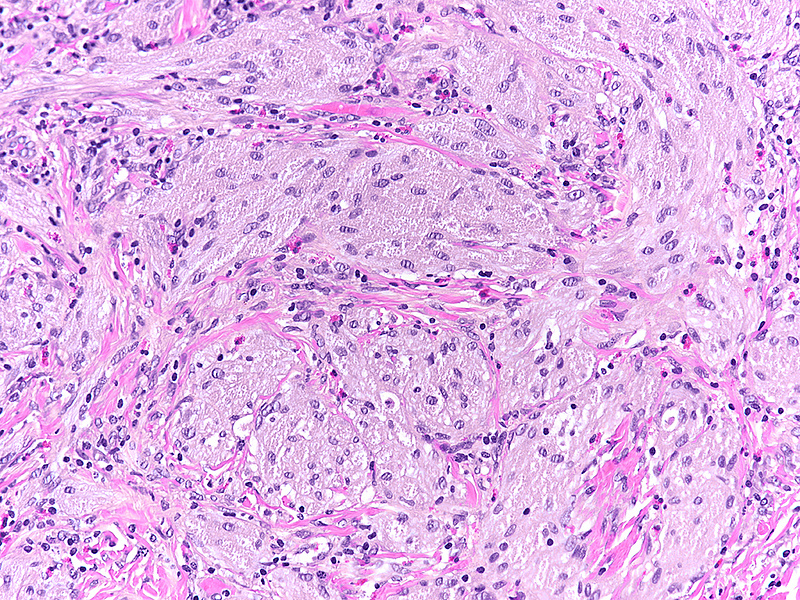

Histologically, we saw a submucosal proliferation of solid nests and ribbons of round to polyhedral cells, measuring approximately 6 mm in largest diameter (Panels A-B). The neoplastic cells generally contained small, uniform nuclei with inconspicuous nucleoli and abundant granular eosinophilic cytoplasm. They were separated by fibrous septa, which contained few inflammatory cells, mostly lymphocytes and few eosinophils (Panel C). In some areas, the neoplastic cells demonstrated cell spindling, still keeping the cytoplasmic features described above (Panel D). The lesion was ill-defined at the base, showing an infiltrative pattern into the surrounding adipose tissue within the submucosal layer (Panels E-F). The neoplastic cells were positive for PAS and strongly immunoreactive for S100-protein (Panels G-H), yet negative for keratin, CD117, DOG-1, and muscle markers, prompting final diagnosis of colonic granular cell tumour.

Granular cell tumors are common lesions in subcutaneous tissue. Gastrointestinal pathologists may encounter this form of peripheral nerve sheath tumour mainly in the oesophagus. In the colorectum, granular cell tumours prevail on the right side (coecum, around the ileocoecal valve, and within the ascending colon). On low power they are either infiltrative or well-defined, involving either the mucosa, submucosa (most common), or both. The cells are characteristically positive for PAS and S100-protein, but may also show positivity for SOX-10, NSE, and synaptophysin.